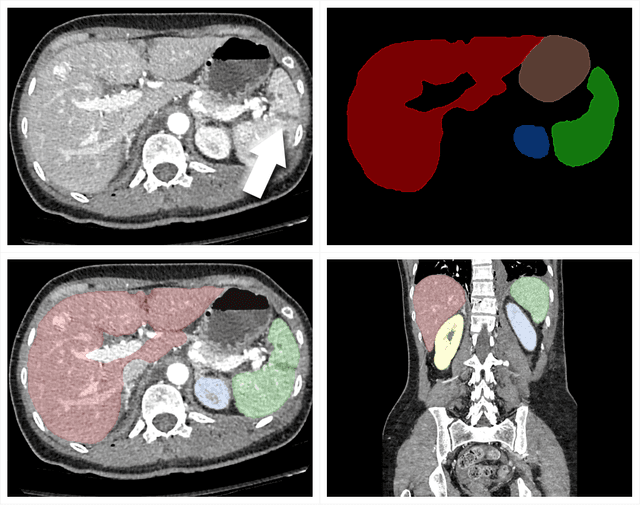

Abstract:The RSNA Abdominal Traumatic Injury CT (RATIC) dataset is the largest publicly available collection of adult abdominal CT studies annotated for traumatic injuries. This dataset includes 4,274 studies from 23 institutions across 14 countries. The dataset is freely available for non-commercial use via Kaggle at https://www.kaggle.com/competitions/rsna-2023-abdominal-trauma-detection. Created for the RSNA 2023 Abdominal Trauma Detection competition, the dataset encourages the development of advanced machine learning models for detecting abdominal injuries on CT scans. The dataset encompasses detection and classification of traumatic injuries across multiple organs, including the liver, spleen, kidneys, bowel, and mesentery. Annotations were created by expert radiologists from the American Society of Emergency Radiology (ASER) and Society of Abdominal Radiology (SAR). The dataset is annotated at multiple levels, including the presence of injuries in three solid organs with injury grading, image-level annotations for active extravasations and bowel injury, and voxelwise segmentations of each of the potentially injured organs. With the release of this dataset, we hope to facilitate research and development in machine learning and abdominal trauma that can lead to improved patient care and outcomes.